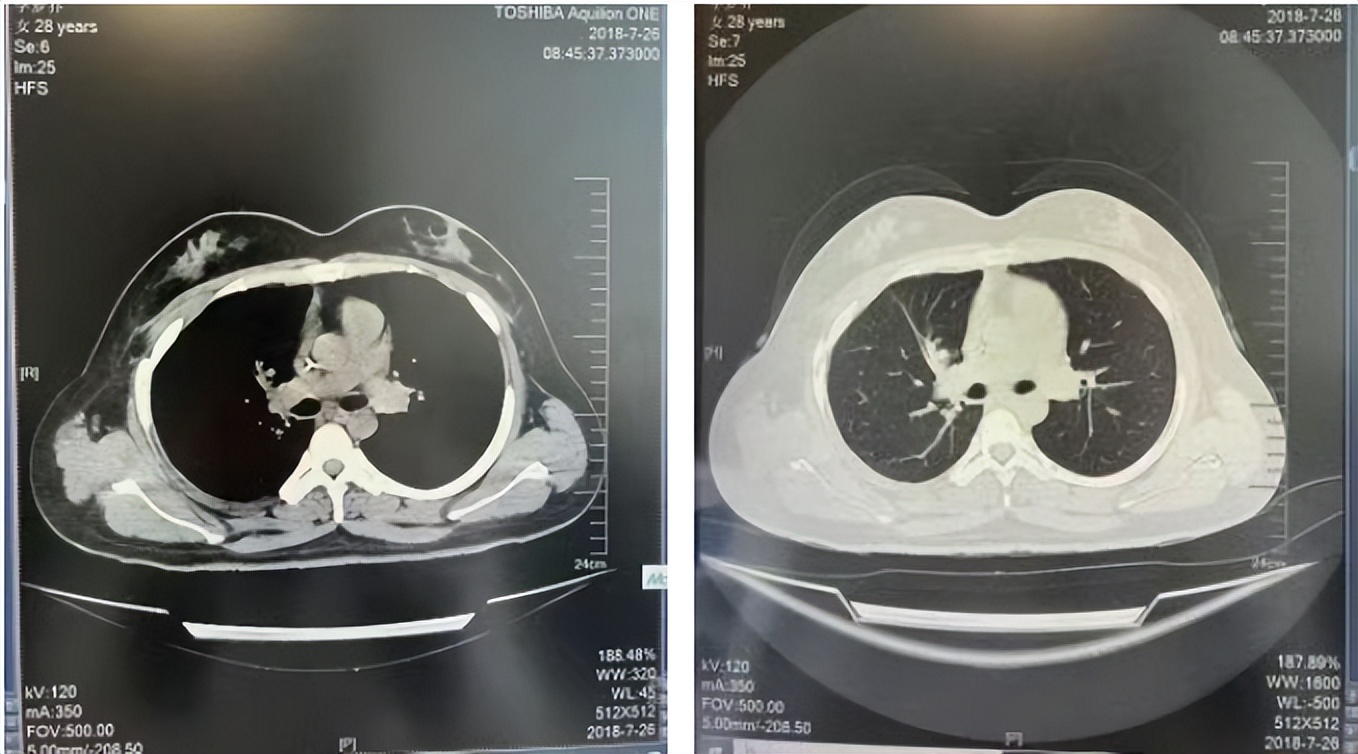

2016年1月复查CT提示支气管截断可见新发小结节,一线治疗采用培美曲塞+DDP方案化疗4周期(培美曲塞3.36,DDP 480mg)。化疗后复查胸部CT:右肺见不规则结节样影,最大层面大小约19mm*8mm,较前比较明显增大,疗效评估PD。2017.3-2017.4予单药多西他赛化疗3周期,疗效评估SD。2018年5月末复查CT提示结节较前增大,评效为PD,2018年6-10月予多西他赛+CBP化疗4周期,疗效评估SD。2022年5月患者出现活动后气短,复查胸部CT示右肺膨胀不良;右侧胸腔积液增多。胸腔积液包埋病理示符合肺腺癌细胞。行NGS基因检测:EML4:exon13-ALK:exon20融合。PD-L1(克隆号22C3)TPS<1%。

诊疗经过:2022年5月始口服克唑替尼3个月,出现肝功能异常(DILI 2级伴临床症状),改用恩沙替尼靶向治疗至今,目前评效为维持PR。恩沙替尼应用期间出现轻度肝功能异常(DILI 1级),对症处理后好转。截止目前PFS 33个月。

2018.07

2022.05

2022.08

2023.05

2024.12